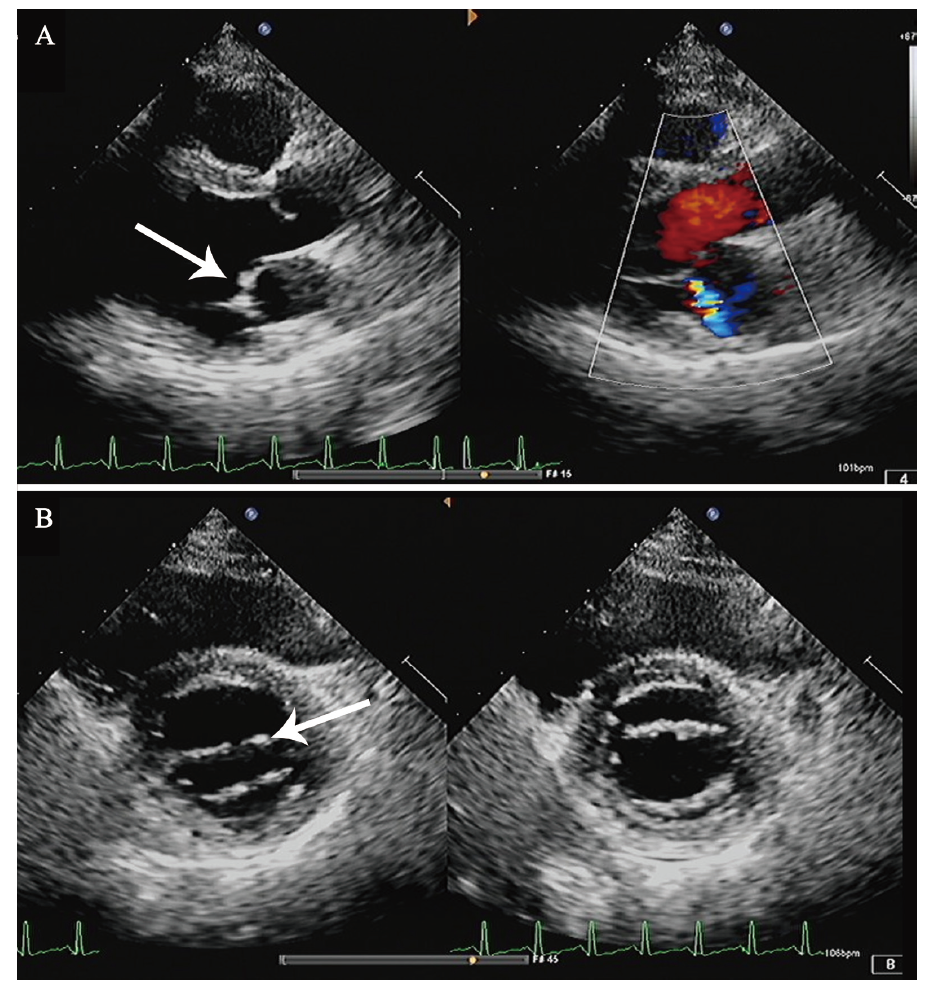

图1 一例SLE继发APS合并Libman -Sacks心内膜炎患者的UCG结果

A:左心室长轴切面示二尖瓣前叶赘生物形成(箭头示);B:二尖瓣水平短轴切面示二尖瓣瓣尖局限性增厚(箭头示)

入院后患者未再出现发热,考虑感染性心内膜炎不能完全除外,于8月11日加用头孢曲松钠抗感染。于8月12日复查UCG,结果示二尖瓣瓣尖局限性增厚。结合患者病史,考虑Libman-Sacks心内膜炎可能,见图1。予以甲泼尼龙治疗,起始剂量为80 mg/d口服,逐渐减量,7 d后减至40 mg/d口服,并予低分子肝素抗凝,加用环磷酰胺0.4 g,每2周1次,同时予营养神经、抑酸护胃治疗。8月20日,患者出现发热,最高体温为38.3℃,下肢搔抓处皮肤破损分泌物病原学培养出嗜麦芽窄食单胞菌,考虑患者发热与此相关,根据药物敏感试验结果改用左氧氟沙星联合复方磺胺甲口恶唑抗感染,之后体温降至正常。8月27日患者午休期间突发头晕、口周麻木、构音不清、吞咽困难,查头颅MRI见一新发的延髓梗死灶。结合患者临床表现、体征及辅助检查,主要诊断为:APS,Libman-Sacks心内膜炎,延髓梗死,SLE。继续予甲泼尼龙40 mg/d抑制免疫、羟氯喹调节免疫,加用环磷酰胺0.4 g (累积量为1.2 g)、低分子肝素抗凝,同时抗血小板聚集、营养神经、抑酸护胃治疗,定期监测国际标准化比值(INR),调整华法林剂量,复查血常规、肝肾功能未见明显异常,凝血酶原时间29.1 s,INR 2.80,无出血表现,患者病情好转,于9月30日出院。出院后门诊随访,一般情况可,至撰稿日无特殊不适。